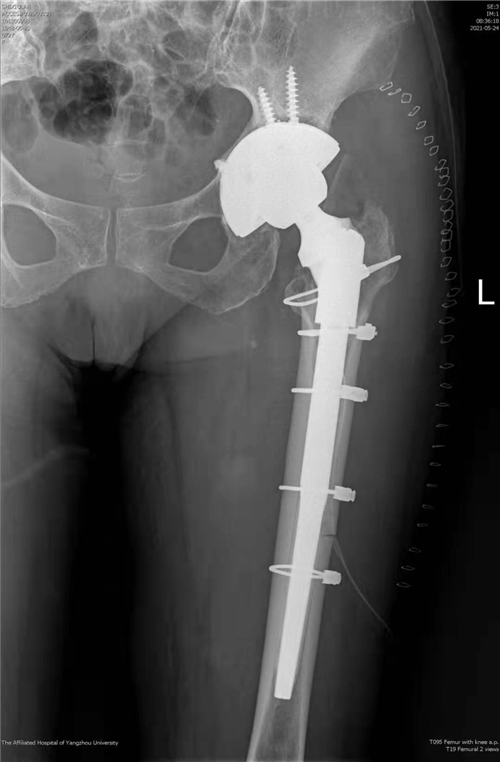

我院首次独立完成复杂全髋关节翻修手术

近日,我院骨科关节组副主任医师徐松诊疗团队成功为一名髋关节假体松动患者实施了全髋关节翻修手术。该手术为我院首次独立完成,打破了我院髋关节翻修需请上级专家会诊或转上级医院手术的传统,填补了我院关节技术的空白,为扬州地区髋关节假体松动患者的治疗提供了便利、减轻了经济负担,为该类患者带来了福音。据了解,患者73岁,女性,7年前因创伤性股骨头坏死接受左全髋关节置换手术治疗,术后髋关节活动一切如常,近3年来患髋逐渐出现疼痛、活动受限,患者渐渐不能行走,长期卧床。因手术难度大、风险高,患者辗转扬州多家医院均遭拒,或建议其上级医院就诊。患者来到我院骨科,接受左全髋关节翻修手术,术后第四天即可下地正常活动,恢复后的患者激动地说:“躺了2年多,我终于可以自己站起来了!”骨科副主任医师徐饶介绍,人工髋关节置换是我院常规开展的一种手术,但人工假体有使用寿命,经长期不规范使用后假体会出现松动,进而进一步影响髋关节功能,情况严重的患者只能长期卧床,患者生活质量受到严重影响,因此需要再次对人工髋关节进行翻新修复,以恢复髋关节的功能。因为人工髋关节的功能是建立在人工假体的稳定性及周围软组织平衡性基础之上,所以对局部骨量及软组织质量要求都比较高,然而松动的假体往往会破坏局部正常的骨结构,引起局部骨量流失,加之初次手术造成的大量骨质缺失、疤痕粘连、软组织解剖结构异常,该类手术难度往往非常大。现在,经过多年技术的积累与沉淀,我院骨科关节组已经完全具备了独立开展此类手术的技术条件,造福了更多扬州百姓。